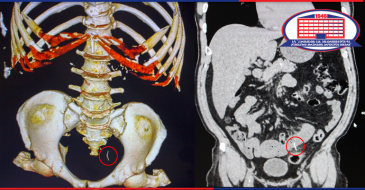

კტ. ენტეროგრაფია საჭმლის მომნელებელი ტრაქტის დეტალური კვლევაა, იგი არაინვაზიური და უმტკივნეულო მეთოდია, რომლითაც ხდება მუცლის ღრუსა და მცირე მენჯის ორგანოების დეტალური აღწერა აქცენტით – მსხვილ და წვრილ ნაწლავებზე,

მათი შრეობრივი და ფუნქციური მდგომარეობის შეფასება, სადაც დახმარებას გაგიწევთ რადიოლოგი თამაზ ჯაოშვილი.

კვლევა წარმოებს კონტრასტის თანხლებით, რისთვისაც საჭიროა პაციენტის წინა დღით მომზადება. შესაბამის ინსტრუქციას პაციენტი მიიღებს ექიმ-რადიოლოგისგან.

შემთხვევები, როცა საჭიროა აღნიშნული კვლევის ჩატარება:

- სისხლდენა ნაწლავიდან;

- ნაწლავის ანთებითი პროცესები;

- ობსტრუქციული პროცესები, გაუვალობა;

- ნაწლავის სიმსივნე;

- კრონის დაავადება;

- კუჭ-ნაწლავის ტრაქტთან დაკავშირებული ნებისმიერი დისკომფორტული მდგომარეობა.